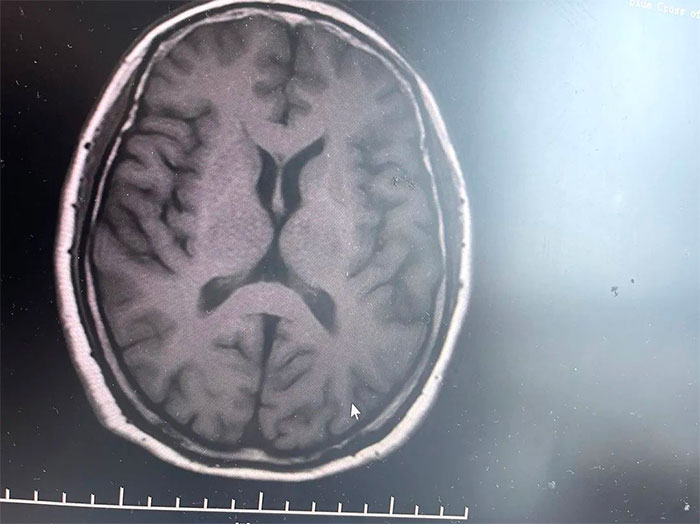

▲ MRI影像提示符合多系統(tǒng)萎縮表現(xiàn)

經(jīng)磁共振(MRI)檢查顯示,林女士橋腦“十字征”、“殼核裂隙征”、“小腦萎縮”,符合多系統(tǒng)萎縮影像表現(xiàn),再次驗證了李振并主任的臨床判斷——多系統(tǒng)萎縮。